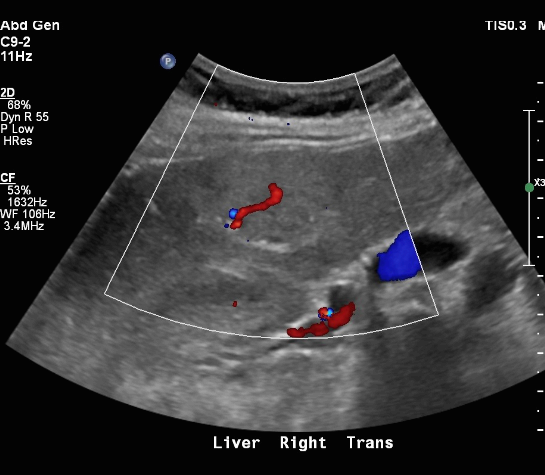

FNH (Focal Nodular hyperplasia) US finding

- isoechoic lesion

- central feeding artery

위에서 보인 초음파소견처럼 FNH는 경계가 명확한 균일한 종괴이며 내부에 섬유성 반흔이 있다. 에코는 저에코를 갖지만 간혹 고에코나 등에코등 다양하게 나타날 수 있으며 피막이 없다. 도플러상 과혈관성을 보이며 정상 간세포조직을 갖는다. 초음파 만으로 간암과 구별할 수 없으므로 혈액검사, CT 와같이 다양한 검사를 통한 진단이 필요하다.